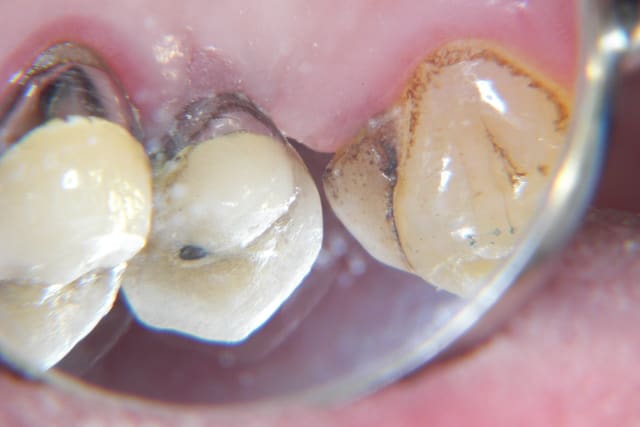

revu le patient hier... tissus mous totalement fibrosés suite à greffe ratée et retraction cicatricielle.

Je m'oriente donc avant sur récupération d'une gencive suffisament épaisse.

Elle consultait car sa 11 est mobile et qu'elle est en avant par rapport aux autres dents.

A l'examen clinique,la patiente n'a pas de carie, tres peu de soins, besoin juste d'un petit détartrage.

La 11 présente une mobilité 2 majorée, elle est en vestibulo position. A la radio, il y a une importante perte osseuse. Il reste uniquement 1/3 de la racine dans l'os et les 2/3 sur les parois de 12 et 21 en rapport avec la 11.